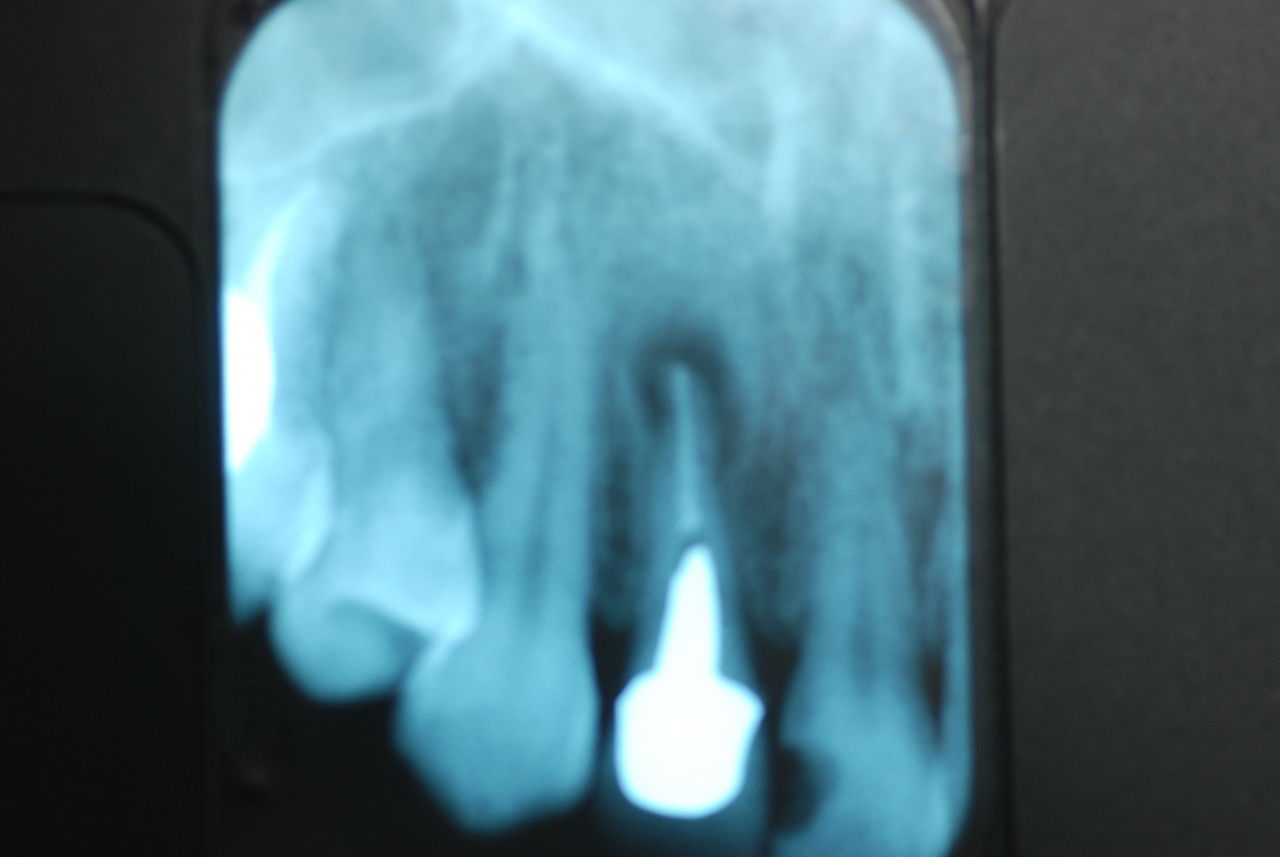

右下の歯は歯の中の治療もあやしいのですが、金属と歯の間がすでに虫歯で崩壊し始めています。

プラークというバイキンと毒素と食べかすの塊が歯の周りや歯茎にまとわりついて虫歯になり且つ重症の歯周病を患っています。